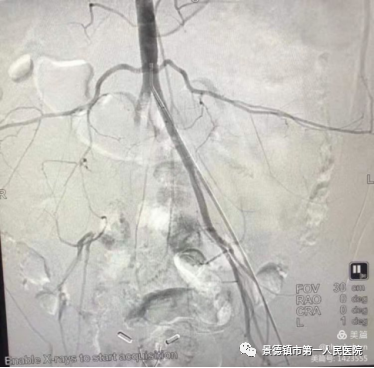

从无到有:部分血管疾病患者再也不用辗转去大城市求医 2018年4月,市一院了解到我市在血管疾病方面的空白与短板后欲组建专门的血管外科,于是如今的血管外科负责人张善忠与万冰受命前往北京学习。张善忠是普外科副主任,从医数十载,有着丰富地临床经验,他与万冰在2018年4月一同前往北京学习先进地血管外科的技术,历时数月学习后在2018年底组建队伍成立血管外科。 市一院血管外科成立后2019年共收治了16名主动脉夹层患者,16名患者无人死亡。要知道,目前已知的许多血管疾病多为突发性疾病,来势汹汹且死亡率高,市一院成立血管外科以前,许多血管疾病患者,只能送往其他城市求医,由于血管疾病的凶险,这些患者中有的病故于求医途中。而在市一院血管外科成立后,2019年收治的16名主动脉夹层病患,由于得到了及时地治疗,无一人死亡。 2021年1月,市一院血管外科便收治了1名血管疾病患者,该患者今年已经80岁,张善忠诊断其患有髂总动脉瘤,该动脉瘤约4.4~4.5公分。张善忠1月30日为其进行微创手术,手术效果较好,该患者在2月4日便办理了出院。出院时该患者与其家人不停地对张善忠表示感谢,并对其医术赞不绝口。 刻不容缓:血管外科是与病魔争分夺秒斗争的战场 许多人对于血管外科疾病不甚了解,有时无法因为无法判断自己身患何病而延误病情。 2019年下半年,张善忠收治了一位因对血管疾病不甚了解而险些截肢的患者。当时该患者整条腿剧烈疼痛,在首次求医时医生初诊为坐骨神经痛。2日后该患者不堪忍受疼痛辗转来到市一院求医,当时张善忠一看到这名患者整条腿疼痛难忍,再看到他的腿部皮肤因缺血呈青紫色,便判断有可能是股动脉栓塞,通过各项检查,得出自己的判断正确,张善忠立即手术将血管内的栓塞取出,保住了患者的腿。他说:“许多市民对血管疾病不了解当成一般的疾病治疗,甚至有些抱着侥幸的念头,觉得多休息就好,但这样的想法往往会延误最佳的治疗时机,比如这位股动脉栓塞的患者,要是再耽搁下去,说不定就要截肢。” 张善忠表示,血管疾病非常危险,其临床表现与一般病症的区别是血管疾病的患者往往会感觉到病灶部位的剧烈疼痛,如果出现这一症状,一定要及时就医,以免延误最佳治疗时机。同时张善忠希望提醒广大市民,如今血管类疾病患者年龄越来越年轻化,与许多人心中的固有印象不同,如今的患者中有许多只有40岁左右。因此希望广大市民在日常生活中注意饮食健康,尤其是需要长期保持同一姿势的市民,在日常生活中需要加强锻炼,预防血管疾病的发生。(稿件来源于瓷都晚报)